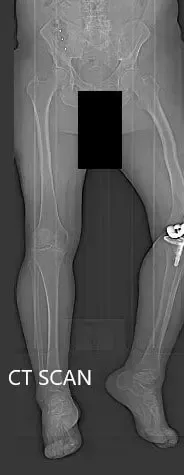

Preoperative topography CT scan images of the lower extremities.

A preoperative CT scan was obtained a few weeks prior to the procedure. Detailed models of the patient’s anatomy were constructed. Accurate bone cuts and offsets were determined to preplan the surgery. Disposable unique jigs and customized implants were made to match the patient’s anatomy.